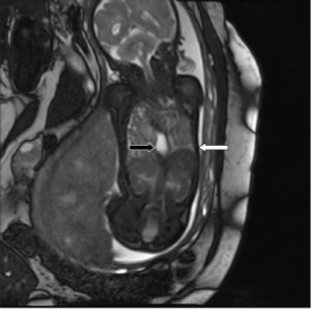

Charts were retrospectively reviewed for observed-to-expected (O/E) values for U/S LHR, MRI FLV measurements, and outcome of the pregnancy and fetus. O/E values normalize measurements to the gestational age of the fetus. MRIs were also retrospectively reviewed by a single pediatric radiologist for location of the stomach. Stomach location was simply defined as all, some, or none of the stomach in the thorax (Figure 2). The primary outcome was survival to discharge. Ultrasound O/E LHR and MRI O/E FLV was compared for all fetuses. An U/S LHR < 1, U/S O/E LHR < 15%, and MRI O/E FLV <25% were considered predictors of poor outcome, and these values were utilized to determine if the various measurements correlated.

Figure 2.MRI demonstrating the entire fetal stomach (black arrow) in the thoracic cavity. The white arrow points to the fetal diaphragm.